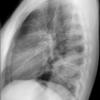

Round pneumonia

different case

Date: 11/28/2009

Views: 5938